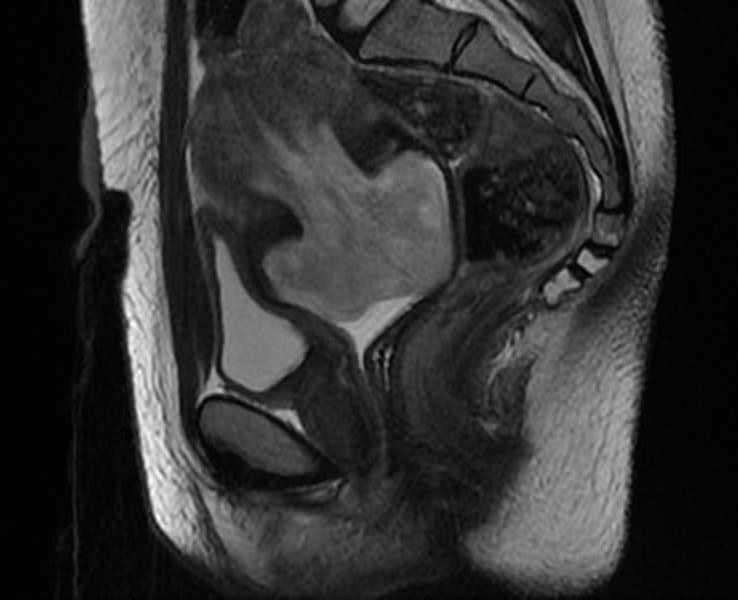

Un  sphacèle intra-vaginal : il s'agit  d'une tumeur  utérine, sous séreuse,

endocavitaire, de 6 x 7 x 5 cm  de  diamètre,  accouchée  par  le  col utérin

nécrosée et infectée. Cette tumeur occupe  la moitié  supérieure  de  la cavité vaginale.

Cliniquement la présente tumeur utérine possède les mêmes caractéristiques d'un fibrome endocavitaire accouché par le col utérin et sphacélé (nécrobiosé), mais l'examen anatomopathologique montre qu'il s'agit d'un léiomyosarcome sphacélé.

Cliniquement : cette tumeur utérine qui a été mise en évidence chez une femme nullipare âgée de 31 ans, était à l'origine de métrorragie chronique évoluant depuis un ans, et aboutissant à une anémie ferriprive et inflammatoire chronique et sévère (hémoglobine à 3 g/dl).

• Anatomopatologie : l'examen histologique de cette tumeur imitant le léiomyome (le fibrome) montre qu'il s'agit d'un léiomyosarcome avec déjà, des métasatses pulmonaires.